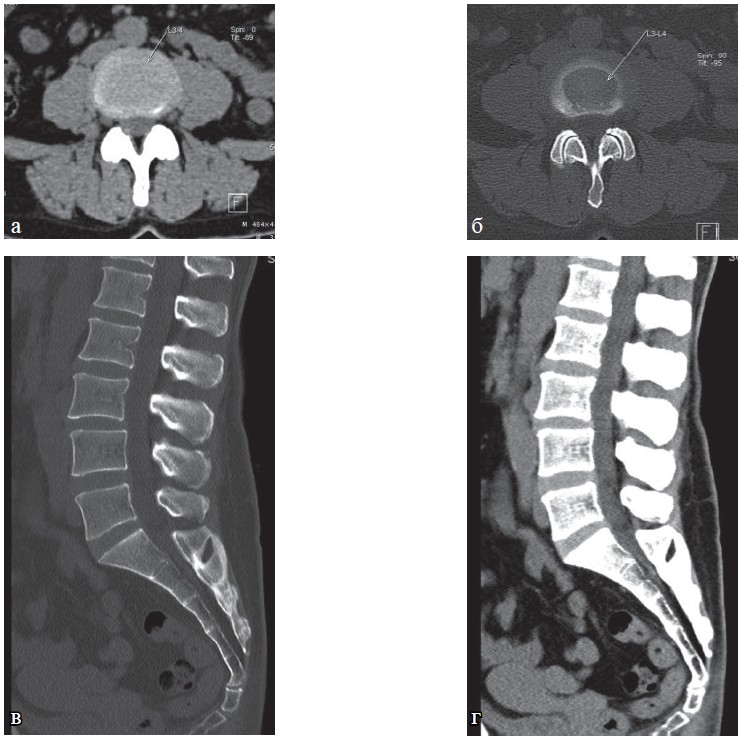

В 3-ю группу были отнесены 83 пациента, у которых выявлены остеохондроз позвоночника III-IV стадии с выраженной дегенерацией диска и его пролапсом более 7 мм, секвестрацией, с выраженными явлениями спондилоартроза и гипертрофией желтых связок (стеноз позвоночного канала, сужение корешковых отверстий), нарушением плотности и структуры кости (остеопороз), спондилолистез II-III степени, болезнь Бехтерева (рис. 7-10).

Рис. 8. КТ шейного отдела позвоночника. Больная Х., 76 лет: а, б — сагиттальная плоскость в статическом положении; в, г — при выполнении функциональных проб; д — аксиальная плоскость. Определяется остеохондроз шейного отдела позвоночника III степени с наличием гипомобильности двигательных сегментов на уровне C3—C7, грыжа межпозвонкового диска С3—4 до 5 мм, остеоартроз унковертебральных сочленений, спондилоартроз, спондилез, передний дегенеративный спондилолистез позвонков С2 I степени, задний дегенеративный спондилолистез позвонков С7 I степени, повышение прозрачности и усиление трабекулярной структуры тел позвонков.

Рис. 9. КТ грудного отдела позвоночника (а—г). Больная С., 63 года. Определяется частичная оссификация передней продольной связки, полная оссификация межостистой связки на уровне грудного отдела позвоночника, костный блок тел позвонков Th4—Th10, костный анкилоз дугоотростчатых суставов Th3—Th12 (проявления болезни Бехтерева), снижение высоты межпозвонковых дисков. Имеются проявления субхондрального склероза замыкательных пластин тел позвонков, обызвествление передней продольной связки, проявления остеоартроза реберно-поперечных суставов, остеоартроза реберно-позвонковых суставов, дугоотростчатых суставов, передний дегенеративный спондилолистез позвонков Th2 и Th3 до 4 мм, S-образный сколиоз грудо-поясничного отдела позвоночника 3 степени.

Учитывая возраст пациентки, выраженность и характер дегенеративных изменений по результатам КТ показано санаторное лечение в режиме минимальной интенсивности физических и ряда физиотерапевтических процедур (щадящий режим).

При проведении КТ пояснично-крестцового отдела позвоночника. Выявляется умеренное снижение высоты межпозвонковых дисков на уровнях L1-5 резкое снижение высоты межпозвонкового диска L5-S1, отмечаются проявления субхондрального остеосклероза замыкательных пластин тел позвонков, остеофиты по краям тел позвонков, задняя диффузная равномерная экструзия межпозвонкового диска L3-4 до 4 мм. Наблюдаются проявления остеоартроза дугоотростчатых суставов уровней L3-S1, передний дегенеративный спондилолистез позвонка L4 до 4 мм, конкремент в нижней группе чашечек правой почки до 4 мм.

Данной пациентке санаторно-курортное лечение показано в щадящем режиме минимального воздействия и интенсивности.